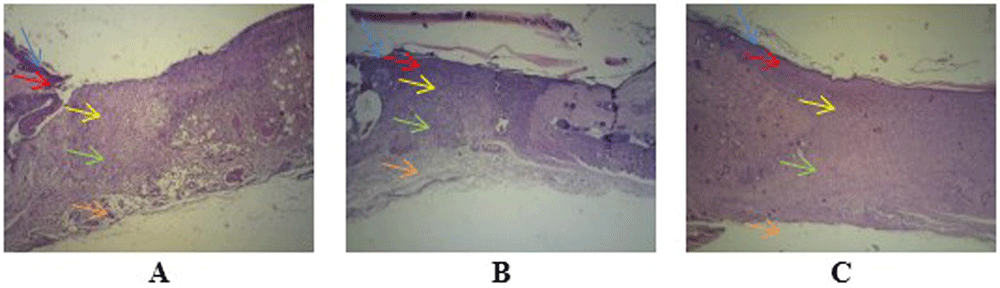

Observation at 40× magnification showed differences in the structure of wounds with healthy skin borders on days two, four, and seven at all perecentage of mucus (Figure 3). Wounds observed on day two showed tissues filled with inflammatory cells without a surface epithelium. Wounds on day four revealed reductions in inflammatory tissue and a thin layer of connective tissue. The surface epithelium covering the wound was fairly thin. On day seven of healing, the wounds showed thick connective tissue formation and a surface epithelium layer clearly covering the wounded area. Inflammatory cells could not be clearly observed on day seven.

Wound healing with gel 96% on day two (A), day four (B), and day seven (C), as determined using histological preparations with hematoxylin–eosin staining at 40× magnification. Blue arrows indicate the epithelium, red arrows indicate the epidermis, yellow arrows indicate the papillary stratum, green arrows indicate the reticular stratum, and orange arrows indicate adipose layers. Observation of angiogenesis was carried out on the papillary and reticular dermal layers of the stratum.